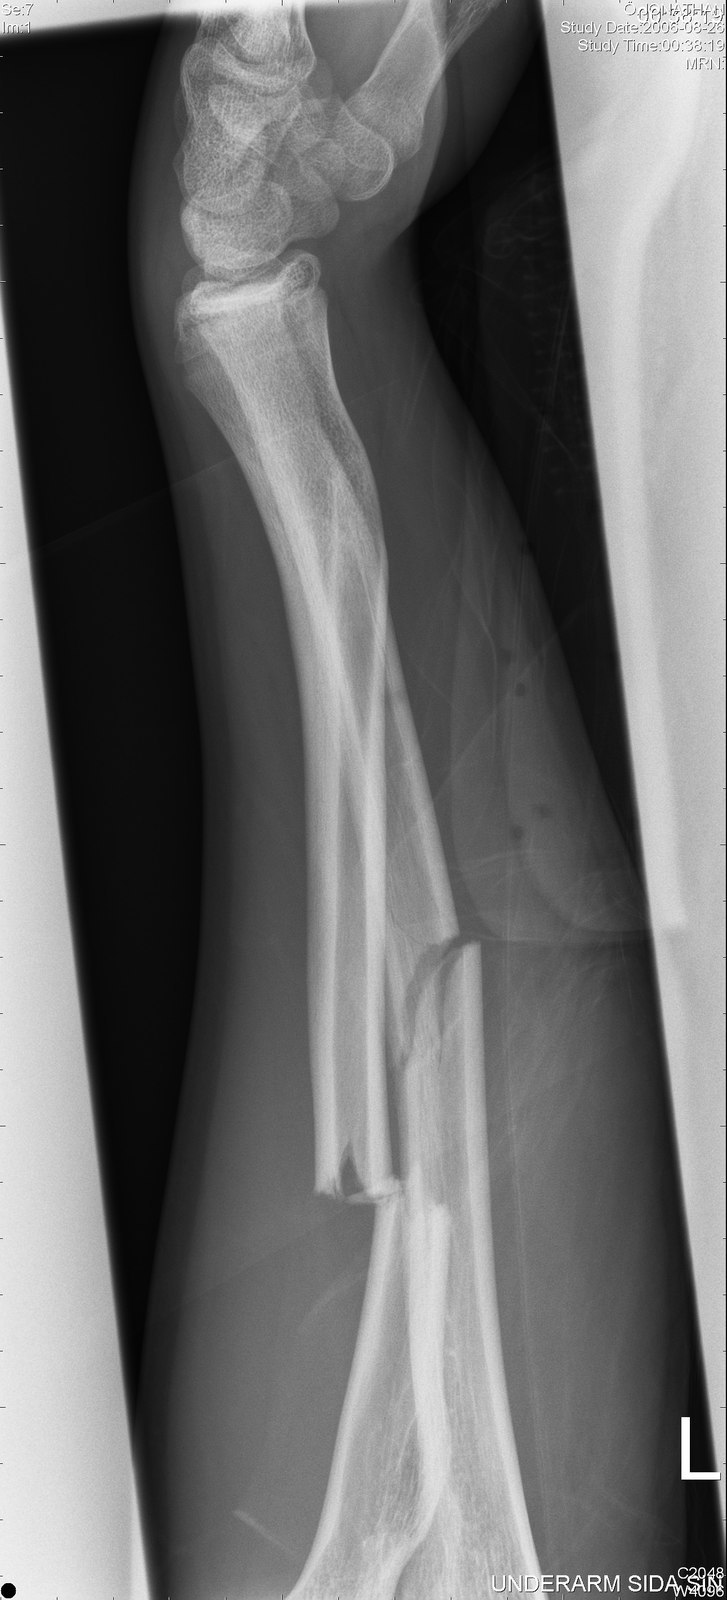

avbruten arm

dom på röntgen

jontex

sundsvall (

Södra Berget